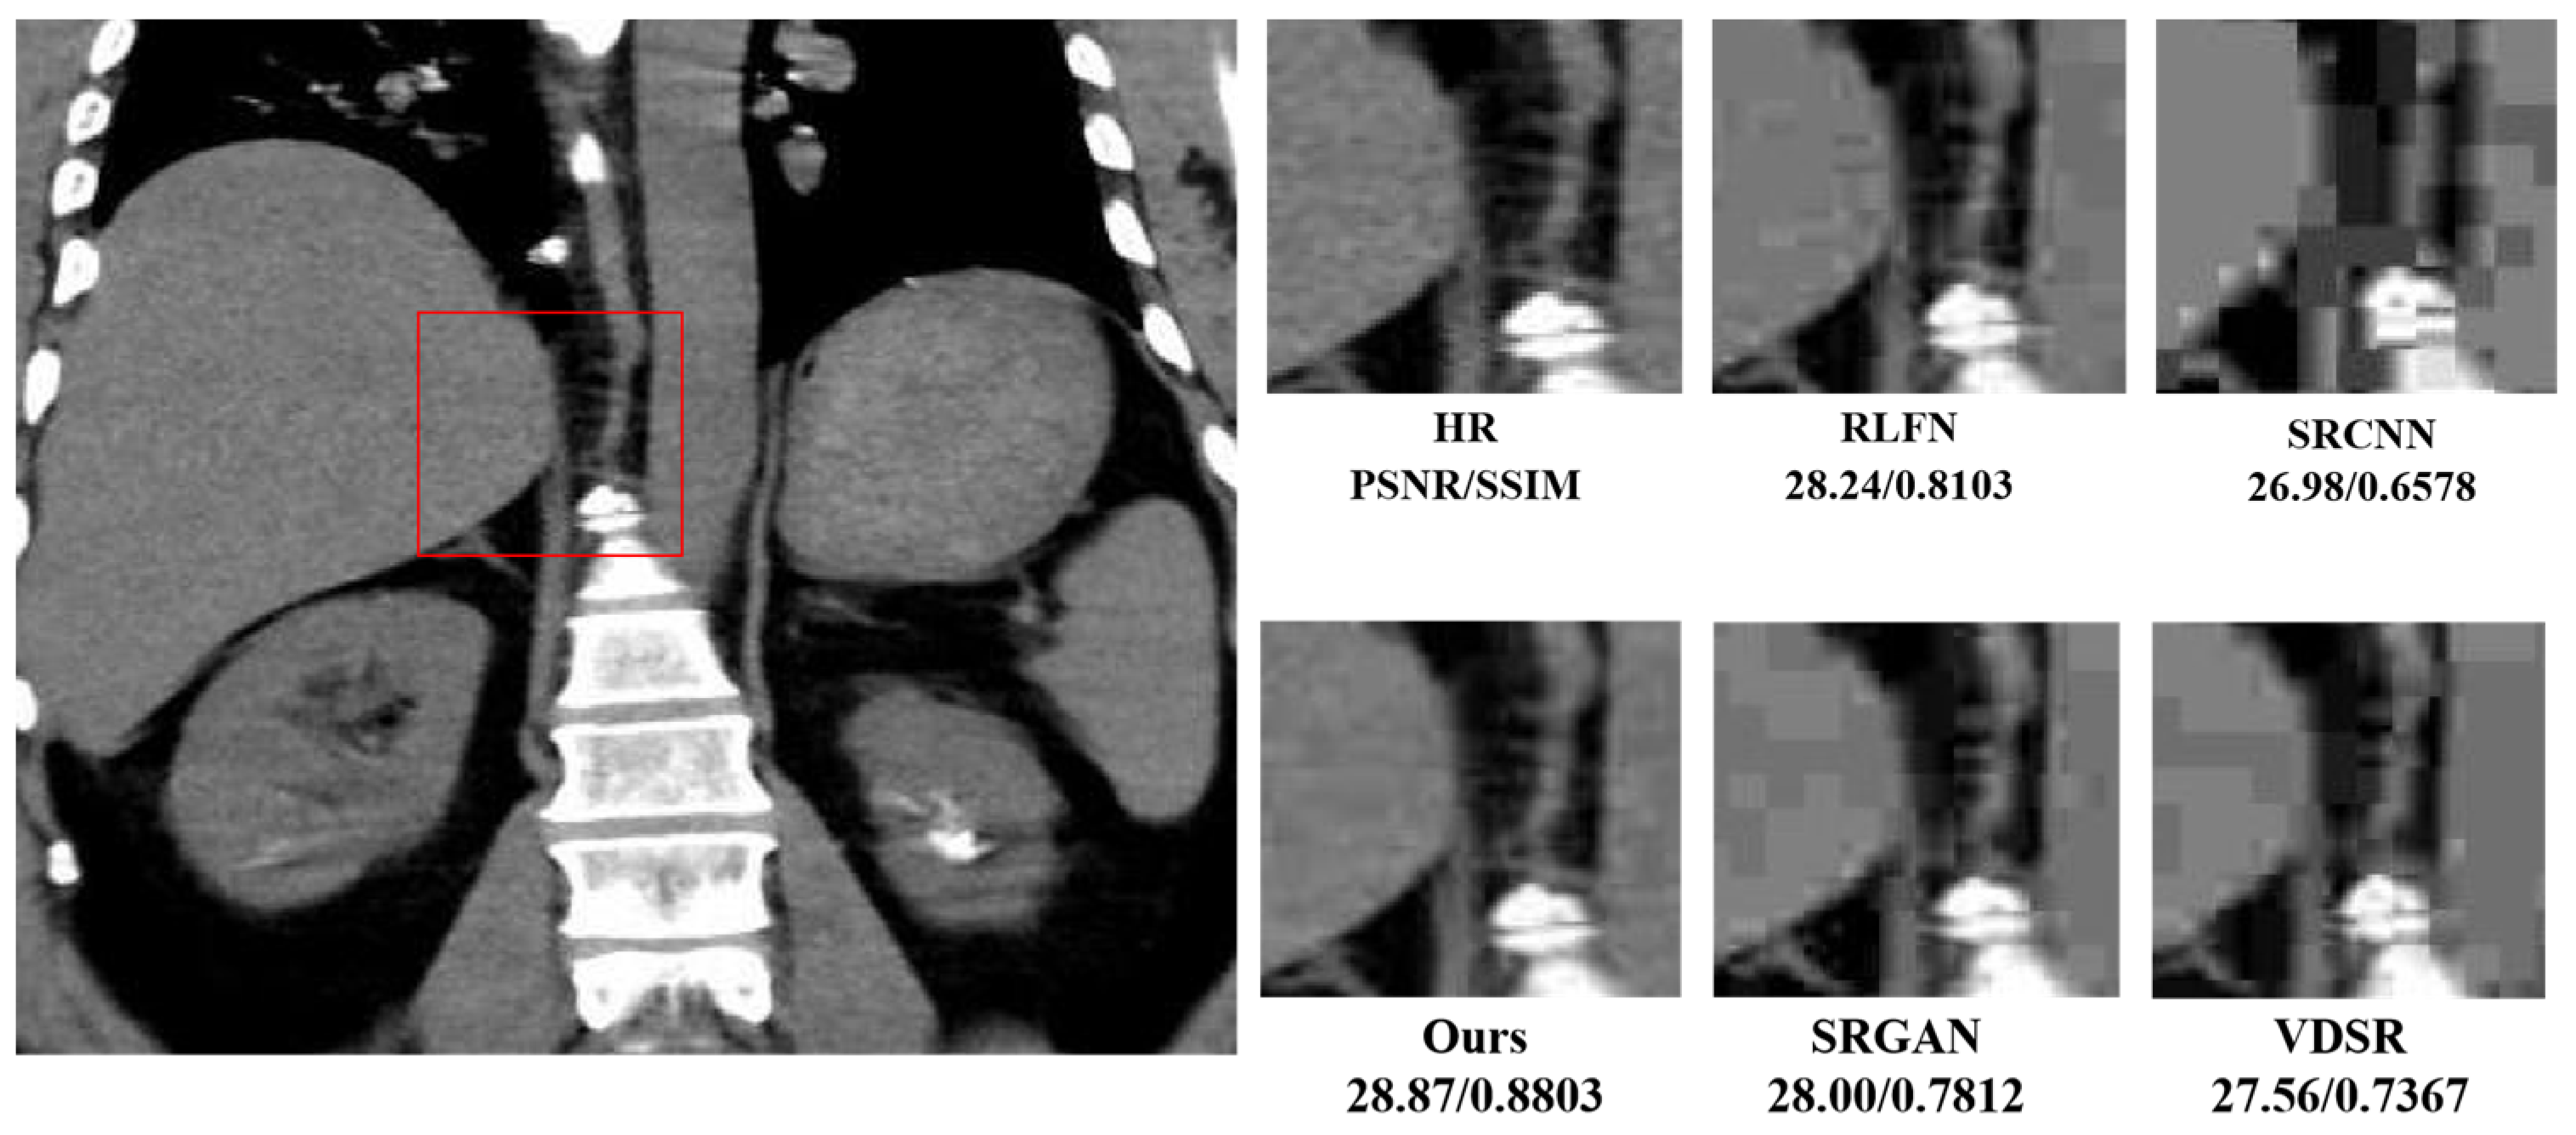

| SRCNN | 57 | 1.90 | 27.78/0.7120 | 28.45/0.7276 | |

| VDSR [12] | 666 | 8.95 | 27.89/0.7165 | 28.61/0.7287 | |

| IMDN [35] | 715 | 20.56 | 27.95/0.7810 | 28.98/0.7301 | |

| RFDN [36] | 550 | 20.40 | 28.12/0.8023 | 29.23/0.7453 | |

| 4× | CARN [37] | 1592 | 39.96 | 27.86/0.7712 | 28.52/0.7282 |

| LapSRN [38] | 502 | 66.81 | 27.15/0.6813 | 28.34/0.7145 | |

| Baseline | 543 | 16.41 | 28.34/0.8230 | 29.37/0.7478 | |

| Ours | 468 | 13.23 | 28.46/0.8256 | 29.48/0.7513 |